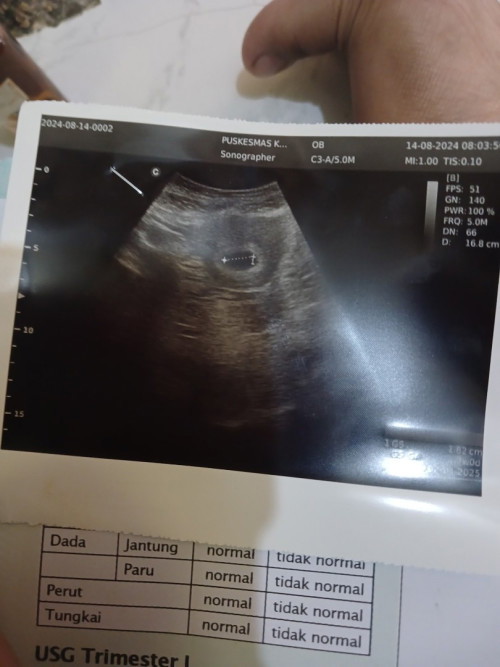

Allhamdullilah aku baru semalem bun usg tapi bukan trasvaginal allhamdullilah ada janin dan djj nya

Alhamdulillah, Bunda. boleh bagi hasil USGnya bunda? semoga bunda sehat selalu bersama Dede bayi